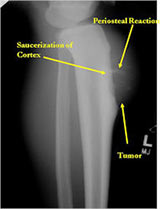

Plain X-Rays:

- Diaphyseal lesion on external surface of bone; medullary canal uninvolved

- Radiolucent mass extending into surrounding soft tissues

- Saucerized cortex with chondroblastic soft tissue mass that is usually primarily radiolucent on plain X-rays

- Periosteal reaction usually most evident feature on surface of bone (Hair on End or Sunburst appearance with spiculated pattern of calcification oriented perpendicular to the bone)

- Cortical thickening at margins of erosion (40%)

- Rarely may have Codman’s triangle

- Spiculated or sunburst periosteal reaction (due to periosteal elevation)

- Partial matrix mineralization may be seen consistent with

- chondroblastic nature

- Rare intramedullary invasion